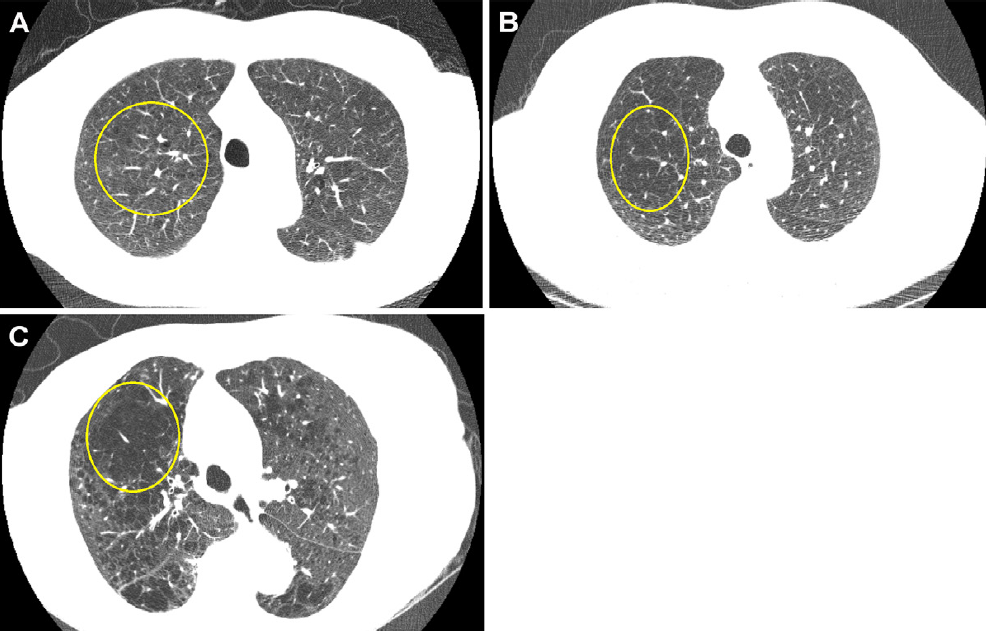

Low-dose CT ties emphysema to mortality in previous smokers

Emphysema found on baseline low-dose chest CT is tied to death related to all causes, chronic obstructive pulmonary disease, and cardiovascular disease, Spanish authors have reported.